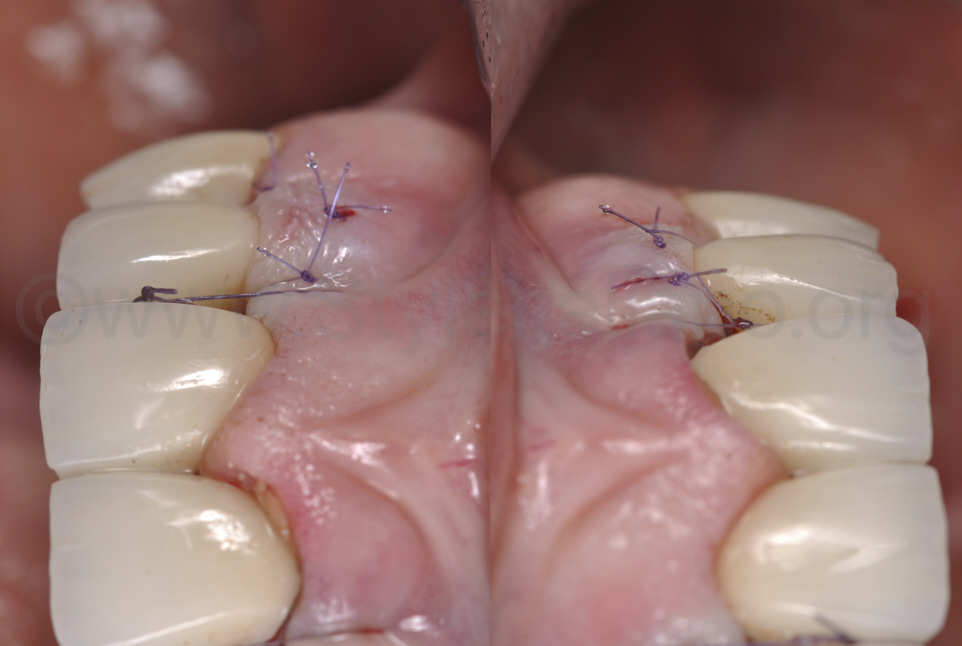

Фото 12.

Після фіксації керамічної реставрації, було накладено підвісні шви, щоб вони підтягували сполучнотканинний трансплантат та поверхневу оболонку в напрямку коронки.